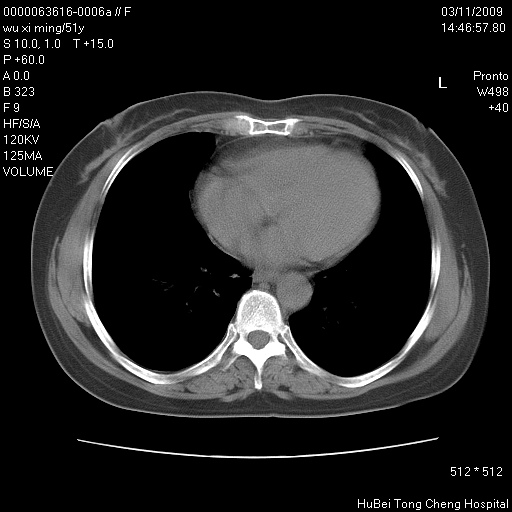

患者 女,51岁。因“胆囊炎,胆囊结石”,行常规术前胸部x线检查发现:右上肺结节病灶,建议行进一步检查。患者无咳嗽、咳痰及咯血等呼吸道症状,近期出现背部疼痛不适。

胸部ct轴位平扫(层厚10mm,螺距1.5,重建间隔10mm;部分层面:层厚3mm,螺距1.0,重建间隔3mm),图像如下:

支持--右肺周围型肺癌---胸椎转移

支持右上肺肺癌并胸椎转移